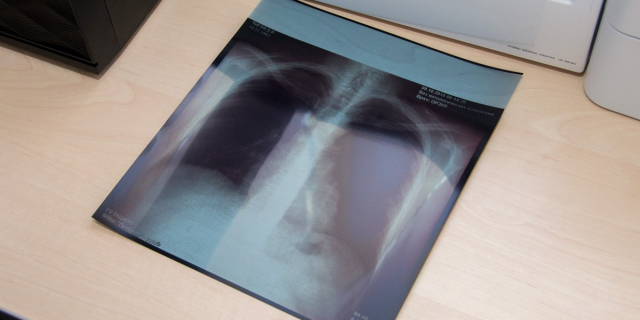

В 2021-м году зарегистрирован самый низкий уровень заболеваемости туберкулёзом за 20 лет За год в республике было выявлено свыше 230 новых случаев 24 Мар., 2022, 17:18 Общество Минздрав Туберкулёз

В прошлом году в Республиканской туббольнице лечились более 350 человек Медучреждение представило итоги работы за 2021 год главе Минздрава 17 Мар., 2022, 12:23 Общество Туберкулёз Минздрав

Кристина Албул: В прошлом году в ПМР зарегистрировано 234 впервые выявленных случая туберкулёза Доклад о диагностике и лечении этого заболевания глава Минздрава ПМР представила на международной научно-практической конференции 25 Фев., 2022, 19:46 Общество Минздрав Год здравоохранения - 2022

Заболеваемость туберкулёзом в Приднестровье идёт на спад В первом полугодии 2020 года было зафиксировано 144 новых случая, за шесть месяцев 2021 года их количество сократилось до 132 15 Сен., 2021, 12:52 Общество Туберкулёз медицина